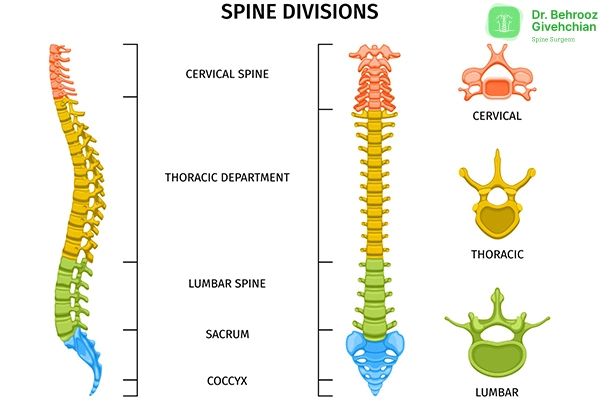

برای اینکه به طور دقیق بتوانیم ناهنجاریهای ستون فقرات را بررسی کنیم باید ابتدا با شکل طبیعی ستون مهرهها آشنا شویم:

قوسهای طبیعی ستون فقرات

در ستون فقرات طبیعی، قوسها به شکل زیر هستند:

- در نمای جانبی (ساژیتال):

- لوردوز گردنی (تقعر به عقب)

- کیفوز سینهای (تحدب به عقب)

- لوردوز کمری (تقعر به عقب)

- کیفوز خاجی (تحدب ثابت به عقب)

- در نمای قدامی (فرونتال):

ستون فقرات باید کاملا عمود و بدون انحراف جانبی باشد. هرگونه انحراف به چپ یا راست ممکن است نشان دهنده اختلالی همچون اسکولیوز باشد.